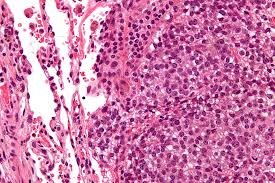

3) 병리학적 소견

• 육안 소견으로는 거칠고 회백색의 덩어리로, 출혈과 낭성 변성이 동반된다. 수질강으로 확산되어 조혈골수를 대체하며, 드물게 관절을 침범할 수 있다.

• 조직학적으로는 다형성(pleomorphism)이 두드러지며, 큰 과염색성(hyperchromatic) 핵과 거대 세포(bizarre tumor giant cells)가 관찰된다. 유사분열이 활발히 일어나며 tripolar form과 같은 비정상적 분열 형태를 보이기도 한다.

• 종양 내 광범위한 괴사가 발생하며, 혈관 내로 침범하는 경향이 있다. 이러한 특성은 종양의 공격성과 전이 가능성을 시사한다.

• 악성 세포는 무기질화되지 않은 골 또는 무기질화된 뼈를 형성하며 이를 통해 진단이 확정된다. 형성된 구조는 fine and lacelike 하거나 broad sheet 또는 trabeculae 형태를 가질 수 있다

Osteosarcoma, Wikimedia Commons